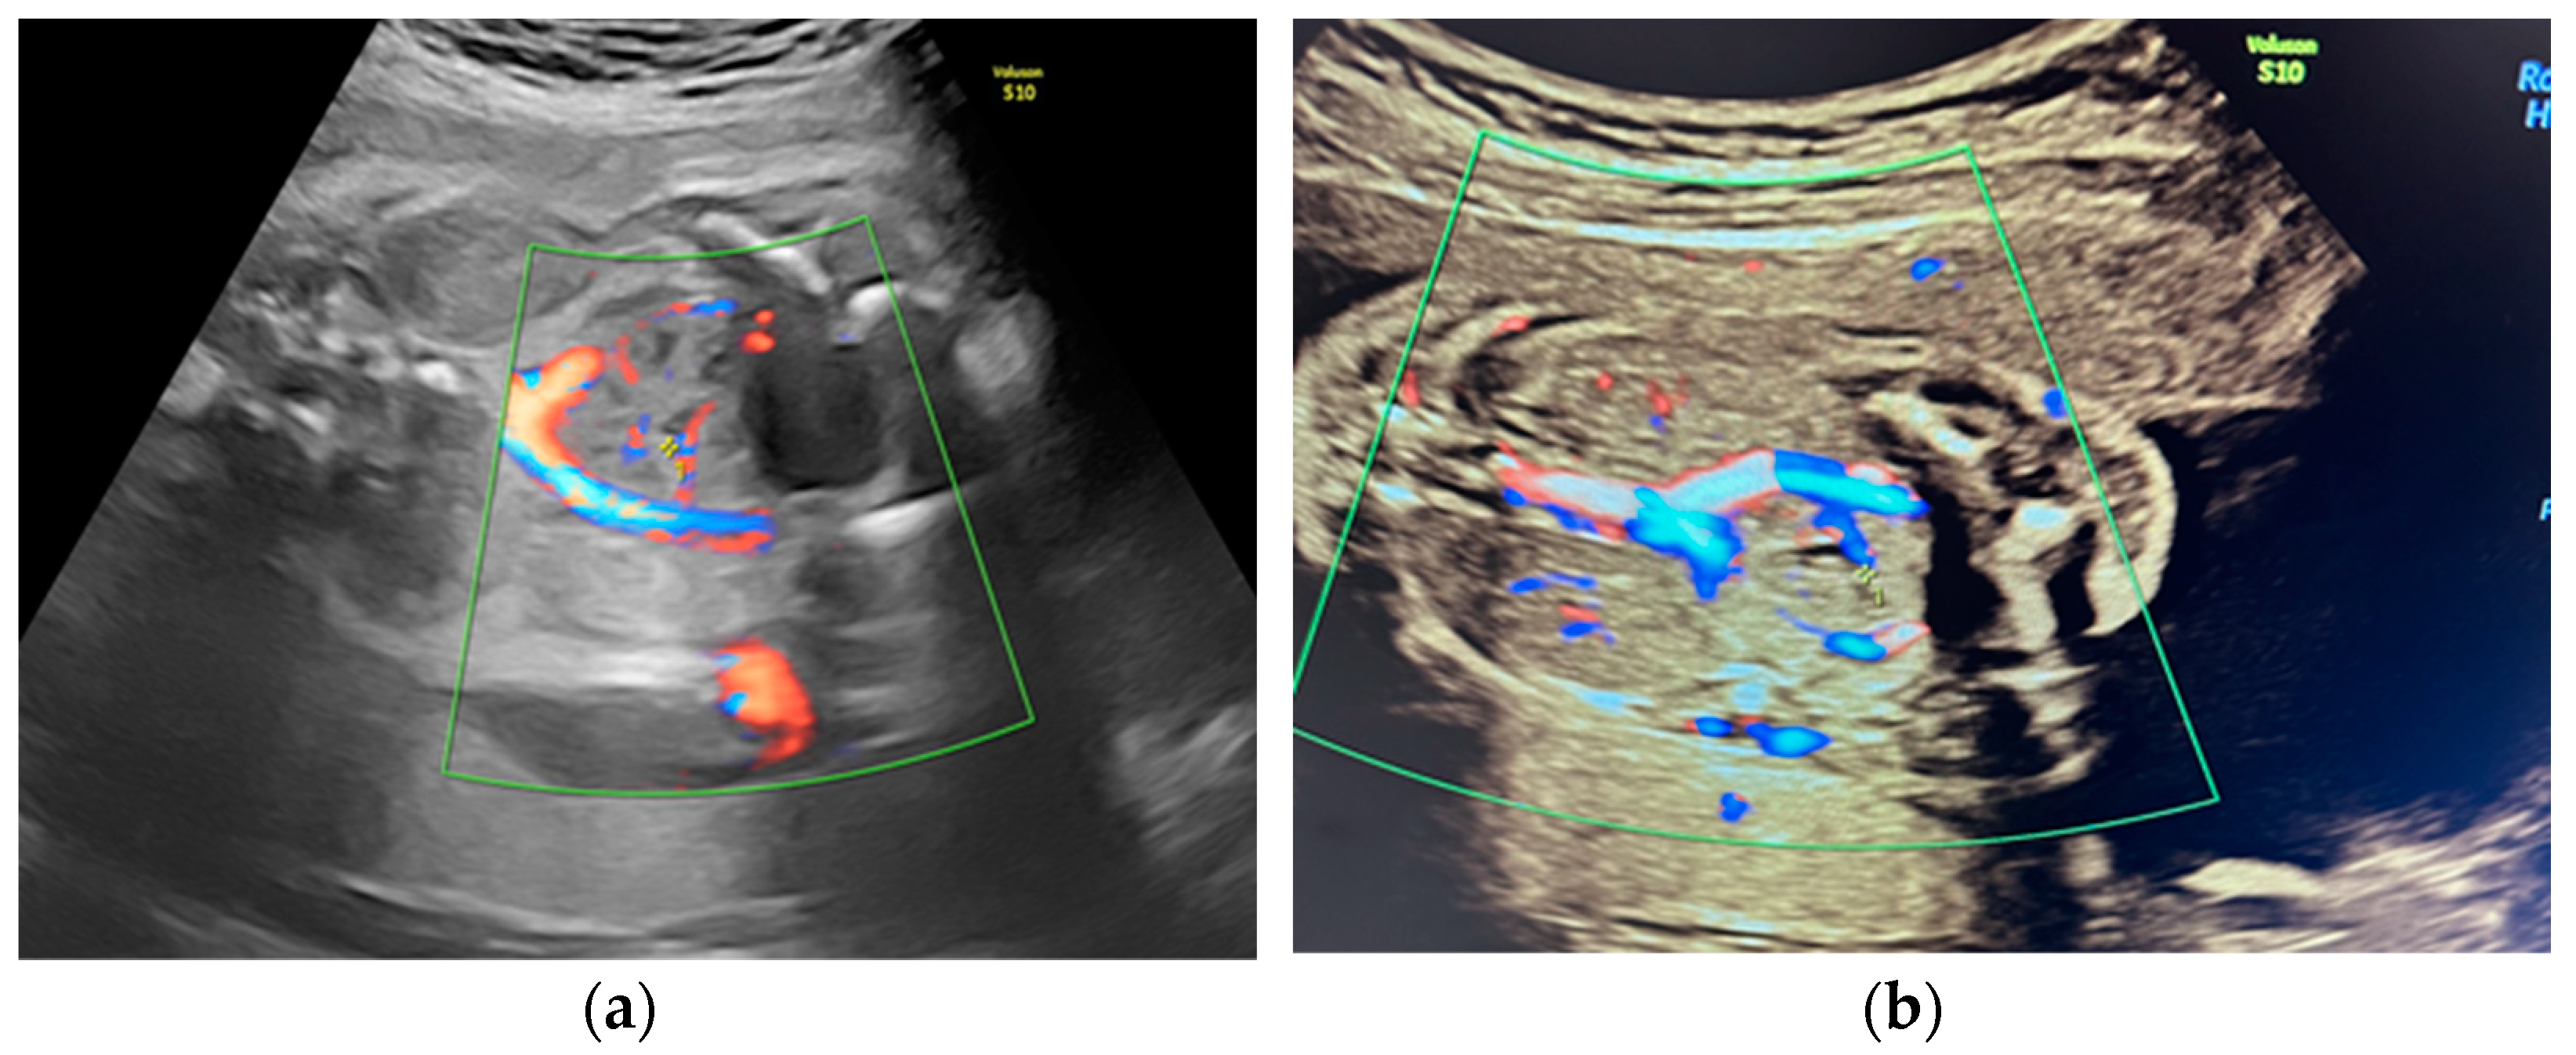

She returned at 20 weeks and 4 days for the second-trimester anomaly scan. Our careful ultrasound examination revealed bilateral empty renal fossa, a normal bladder, and normal amniotic fluid volume. No other fetal anomalies were detected, and the fetus was normally grown. Renal tissue was found in the fetal pelvis, close to the bladder and to the right (Figure 1). On a transvaginal scan, we demonstrated a duplex kidney with two renal pelvises (Figure 2a,b). The artery supply was seen coming from the internal iliac artery (Figure 3a,b). We offered invasive testing, but the patient declined. A fetal echocardiography was also performed, which showed no abnormalities of the fetal heart.

This case is peculiar because of the presence of both kidneys in the pelvis, the right one having an anomaly of fusion with two collecting systems and the left one being small, and the vascular supply of the right duplex kidney was aberrant, branching from the internal iliac artery.

Figure 3. (a,b) Vascular supply of the pelvic kidney from internal iliac artery.